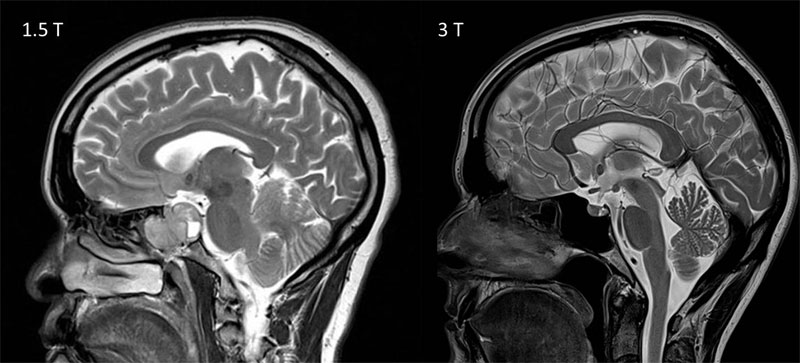

Пироговский Центр в сотрудничестве со Сколковским институтом науки и технологий, ООО «Сбермедии» и ООО «Иммерсмед» продолжил исследовать возможности применения цифровых инноваций в медицине. Ведутся проекты по использованию современных технологий, включая машинное обучение, для обработки результатов магнитно-резонансной томографии и электроэнцефалографии. Цель проекта — изучение причин и своевременная диагностика эпилепсии, что позволит не только приоткрыть тайны функциональных структур головного мозга, но и вовремя начать прием наиболее подходящих медикаментов, провести нейрохирургическую операцию, повысив тем самым вероятность полного излечения пациентов.

- Современная нейровизуализация (МРТ, ОФЭКТ, SISCOM)